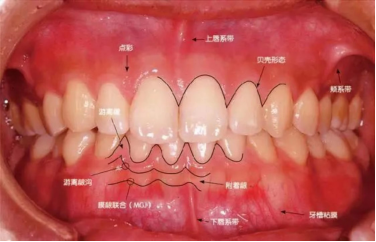

健康牙龈